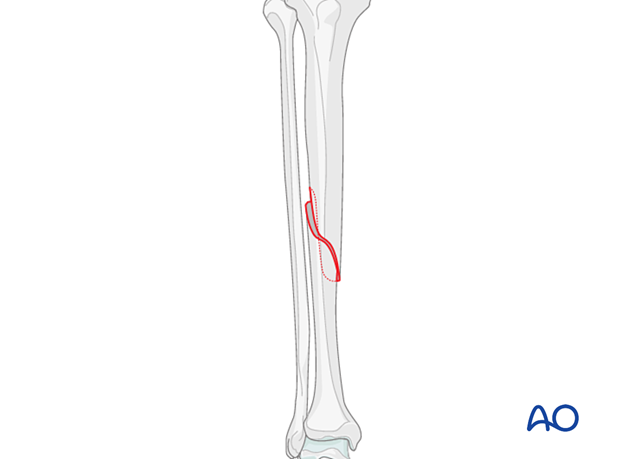

This fracture is classified as an AO/OTA 42A1 fracture. These are simple diaphyseal fractures of the tibia with a spiral fracture line, located at various levels of the diaphysis.